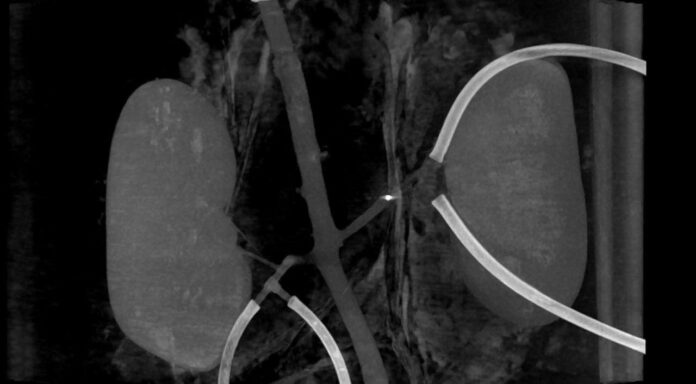

An X-ray image shows a millirobot making its way through a blood vessel. (University of Twente)